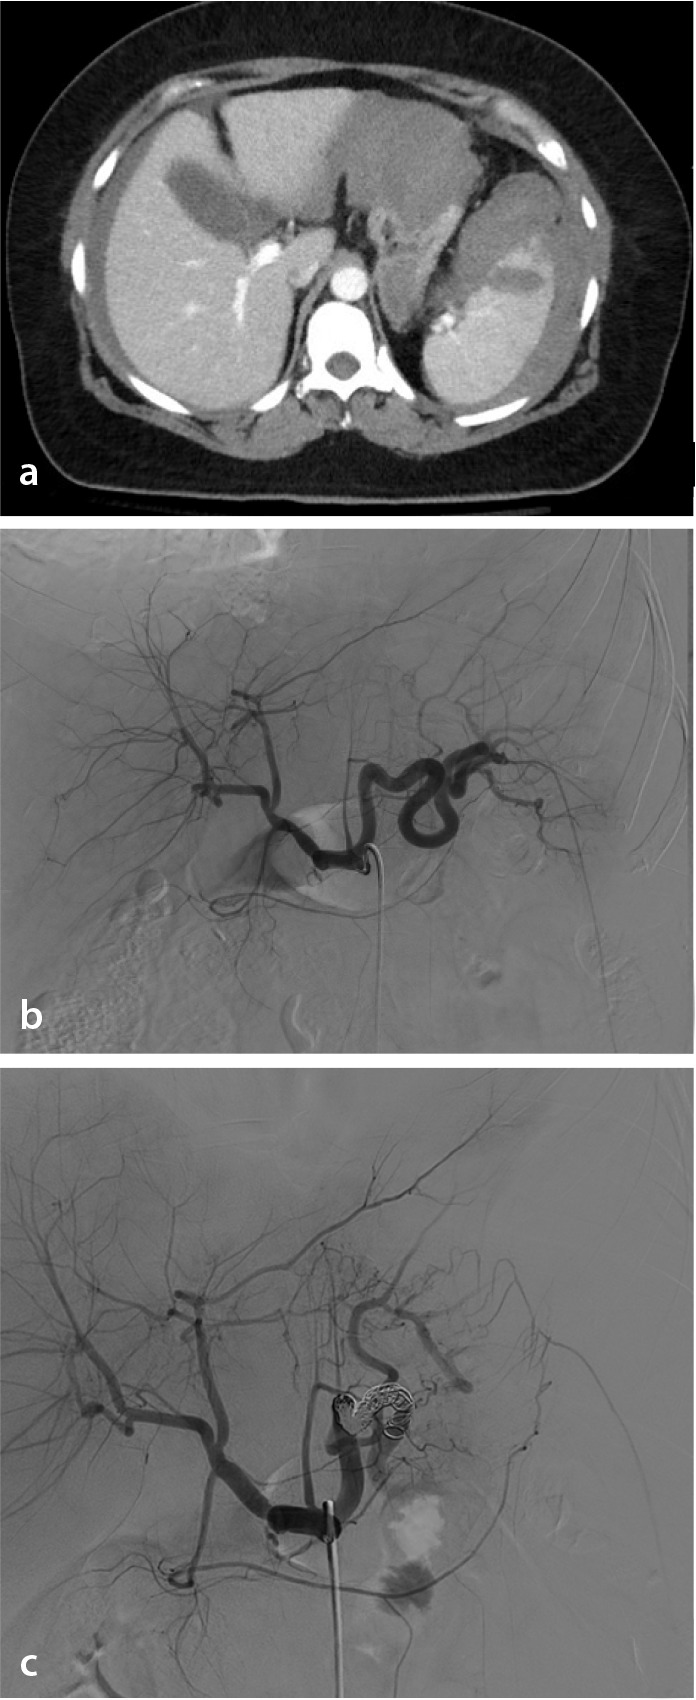

Abstract Image